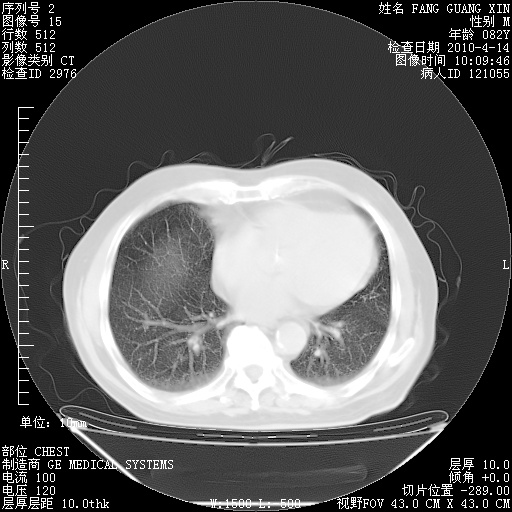

肺部CT平扫未见异常。